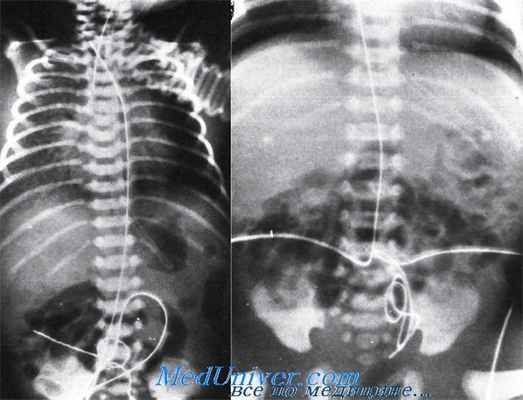

Различные неправильные положения катетера в пупочной артерии: слева — близость к почечным артериям на уровне II поясничного позвонка; справа — катетер в левой плечеголовной артерии.

Различные неправильные положения катетера в пупочной артерии: слева — катетер в правой плечеголовной артерии; справа — катетер в тазовой артерии.